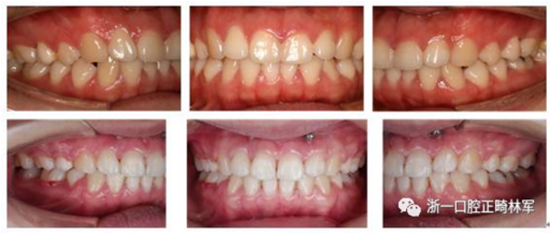

我們給她拔了4顆牙第一前磨牙,打了骨釘,來(lái)排齊牙齒,內(nèi)收前牙,改善側(cè)貌,后期又做了牙齦小手術(shù),幫她把露齦笑也解決了,最后治療結(jié)束時(shí)她不僅牙齒整齊、咬合良好,而且側(cè)貌漂亮,治療前嘴巴前突、下巴后縮、露齦笑的問(wèn)題都改善了,她對(duì)此很滿意。一起來(lái)看看效果吧!

治療前后面像、口內(nèi)像對(duì)比

8.png

9.png

10.png

有了更柔和的側(cè)貌和更甜美的微笑,相信這個(gè)女生今后會(huì)更自信,人生會(huì)更精彩。

矯正不僅僅可以獲得整齊的牙齒,我們正畸醫(yī)生的目標(biāo)是美觀、功能、穩(wěn)定、健康。站得更高、看的更遠(yuǎn),矯正改變?nèi)松?/p>